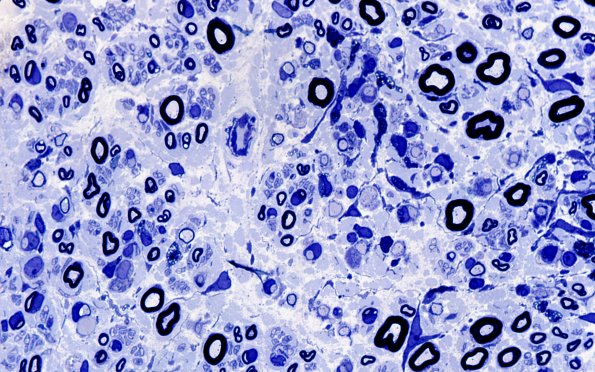

Washington University Experience | PERIPHERAL NEUROPATHY | 7A GUILLAIN-BARRE SYNDROME (GBS) | 7A4 GBS (Case 7) Plastic 100X 3

There are many regions in which the number of demyelinated and thinly remyelinated axons are markedly increased. (Plastic sections)